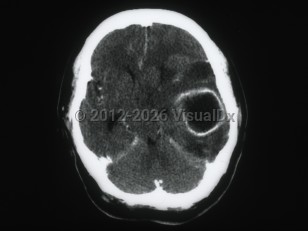

Subarachnoid hemorrhageSubarachnoid hemorrhage